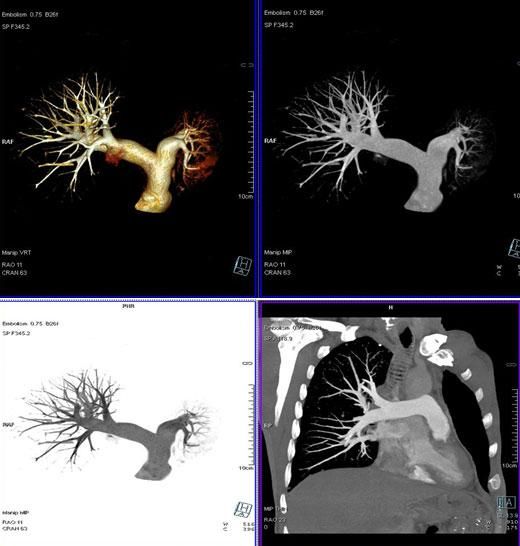

二、多層螺旋CT頭頸部及體部血管成像技術:

該機掃描覆蓋範圍廣、時間短,多種後處理分析軟件能顯示各血管細小分支,可以清晰顯示動脈瘤、動脈夾層、血管畸形、血管狹窄及動脈粥樣硬化斑塊等,适用于頭頸部血管成像、肺動脈成像、胸腹部血管成像及四肢血管成像。

3、肺動脈血管成像:

4、腎動脈血管成像(腎動脈狹窄):

5、下肢動脈血管成像: